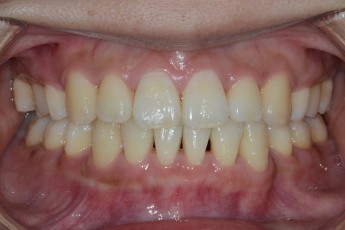

Before

After